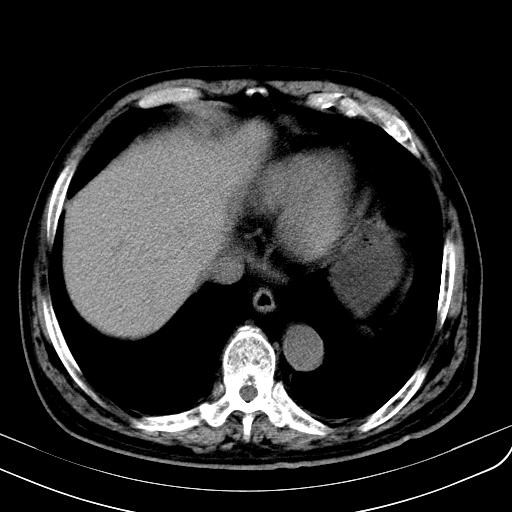

胃底靠近胃大弯处可见一圆形软组织影,直径为3.45cm,ct值约为30.1hu

边缘光滑,密度均匀,良性占位,首先考虑平滑肌瘤。

边缘光滑,密度均匀,良性占位,首先考虑平滑肌瘤。其实平滑肌瘤也是间质瘤的一种